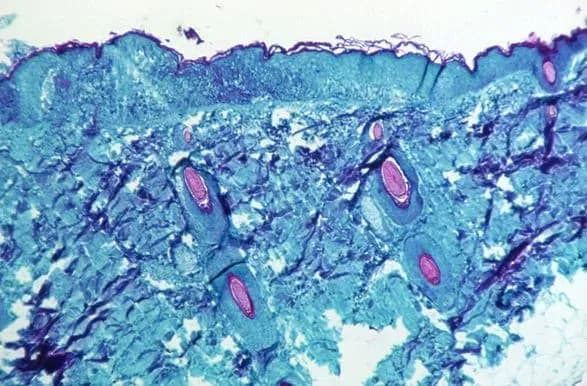

КИЇВ. 23 травня. УНН. Всесвітня організація охорони здоров'я не має доказів того, що вірус мавпячої віспи мутував, заявили у понеділок керівники агентства ООН, зазначивши, що інфекційне захворювання, ендемічне в Західній та Центральній Африці, має тенденцію не змінюватися. Про це УНН пише з посиланням на Reuters.

За даними ВООЗ, спалахи нетипові, оскільки відбуваються у країнах, де вірус не циркулює регулярно. Вчені намагаються зрозуміти походження випадків і чи щось змінилося у вірусі.

Віспа мавп - це інфекційне захворювання, що зазвичай протікає в легкій формі і ендемічне в деяких частинах Західної та Центральної Африки. Він передається при тісному контакті, тому його можна легко стримати за допомогою таких заходів, як самоізоляція і гігієна.